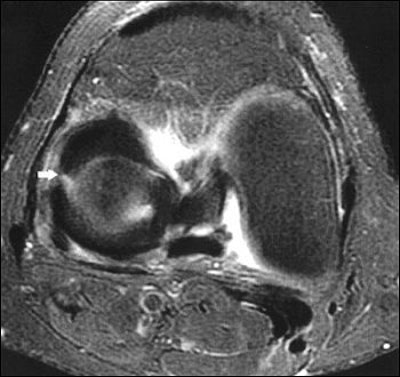

| Sixty-six-year-old man with radial tear of lateral meniscus. Above, axial fat-saturated fast spin-echo proton density-weighted image (TR/TE, 2,717/54; slice thickness, 4 mm) of right knee shows well-defined linear increased intensity (arrow) in body of lateral meniscus starting from free edge. Below, coronal fat-saturated fast spin-echo proton density-weighted image (3,750/60; slice thickness, 4 mm) shows tear as vertical defect in body of lateral meniscus (arrow). Tarhan NC, et al, "Meniscal Tears: Role of Axial MRI Alone and in Combination with Other Imaging Planes," (AJR 2004, Vol. 183, pp. 9-15). |